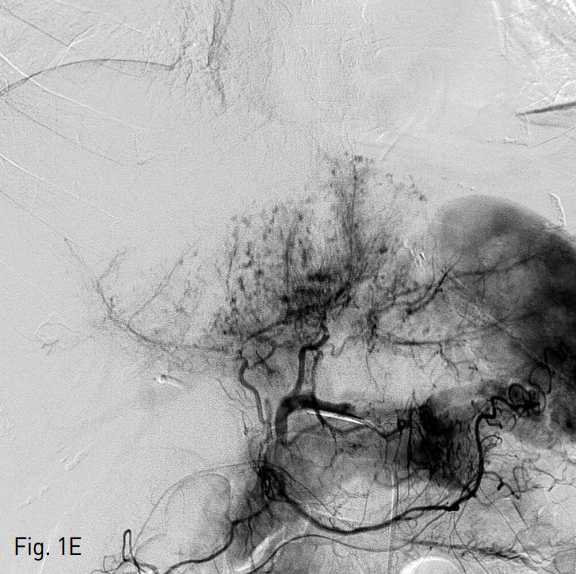

혈관조영술과 색전술을 위하여 우측 총 대퇴동맥을 통해 5 Fr RH catheter를 간동맥에 위치시킨 후 카테터 내에 2.2 Fr 미세도관을 삽입하여 다발성의 점상출혈이 있는 부위에 대하여 gelatin particle을 이용하여 색전술을 시행하였다. 색전술 시행 다음날, 다시 복부팽만과 hemogloin 수치 감소(8.8g/dL → 8.0g/dL)가 발생하여 복부 CT를 시행하였다. 추적 복부 CT상 간 내 혈종의 양이 증가되었고 2, 3번 segment에도 새롭게 다발성의 점상출혈이 보였다 (Fig. 1D). 새로이 보이는 Left lobe의 다발성 점상출혈을 확인하기 위하여 간동맥 혈관조영술을 시행하였으나 명확하게 출혈소견이 보이지 않았기에 간 동맥 외의 다른 동맥을 통한 출혈부위를 찾기 위하여 5 Fr Headhunter angiocatheter를 이용하여 우측 내유동맥의 혈관조영술을 시행하였고 (Fig. 1E, F) 내유동맥 조영술상에서 간 좌분절의 다발성 점상출혈을 확인하고 2.2 Fr 미세도관으로 진입하여 gelatin particle을 이용한 색전술 시행하였다. 이후에 환자는 더 이상의 출혈소견 없이 호전되었다.

E. A celiac angiography revealed still remaining multifocal active bleeding foci at the left hepatic segment of liver.

F. Subsequent right Internal mammary angiography revealed multifocal active bleding foci at the left hepatic segment of liver. Arterial embolization with gelfoam particle was done. And the general condition of patient was improved (not shown).